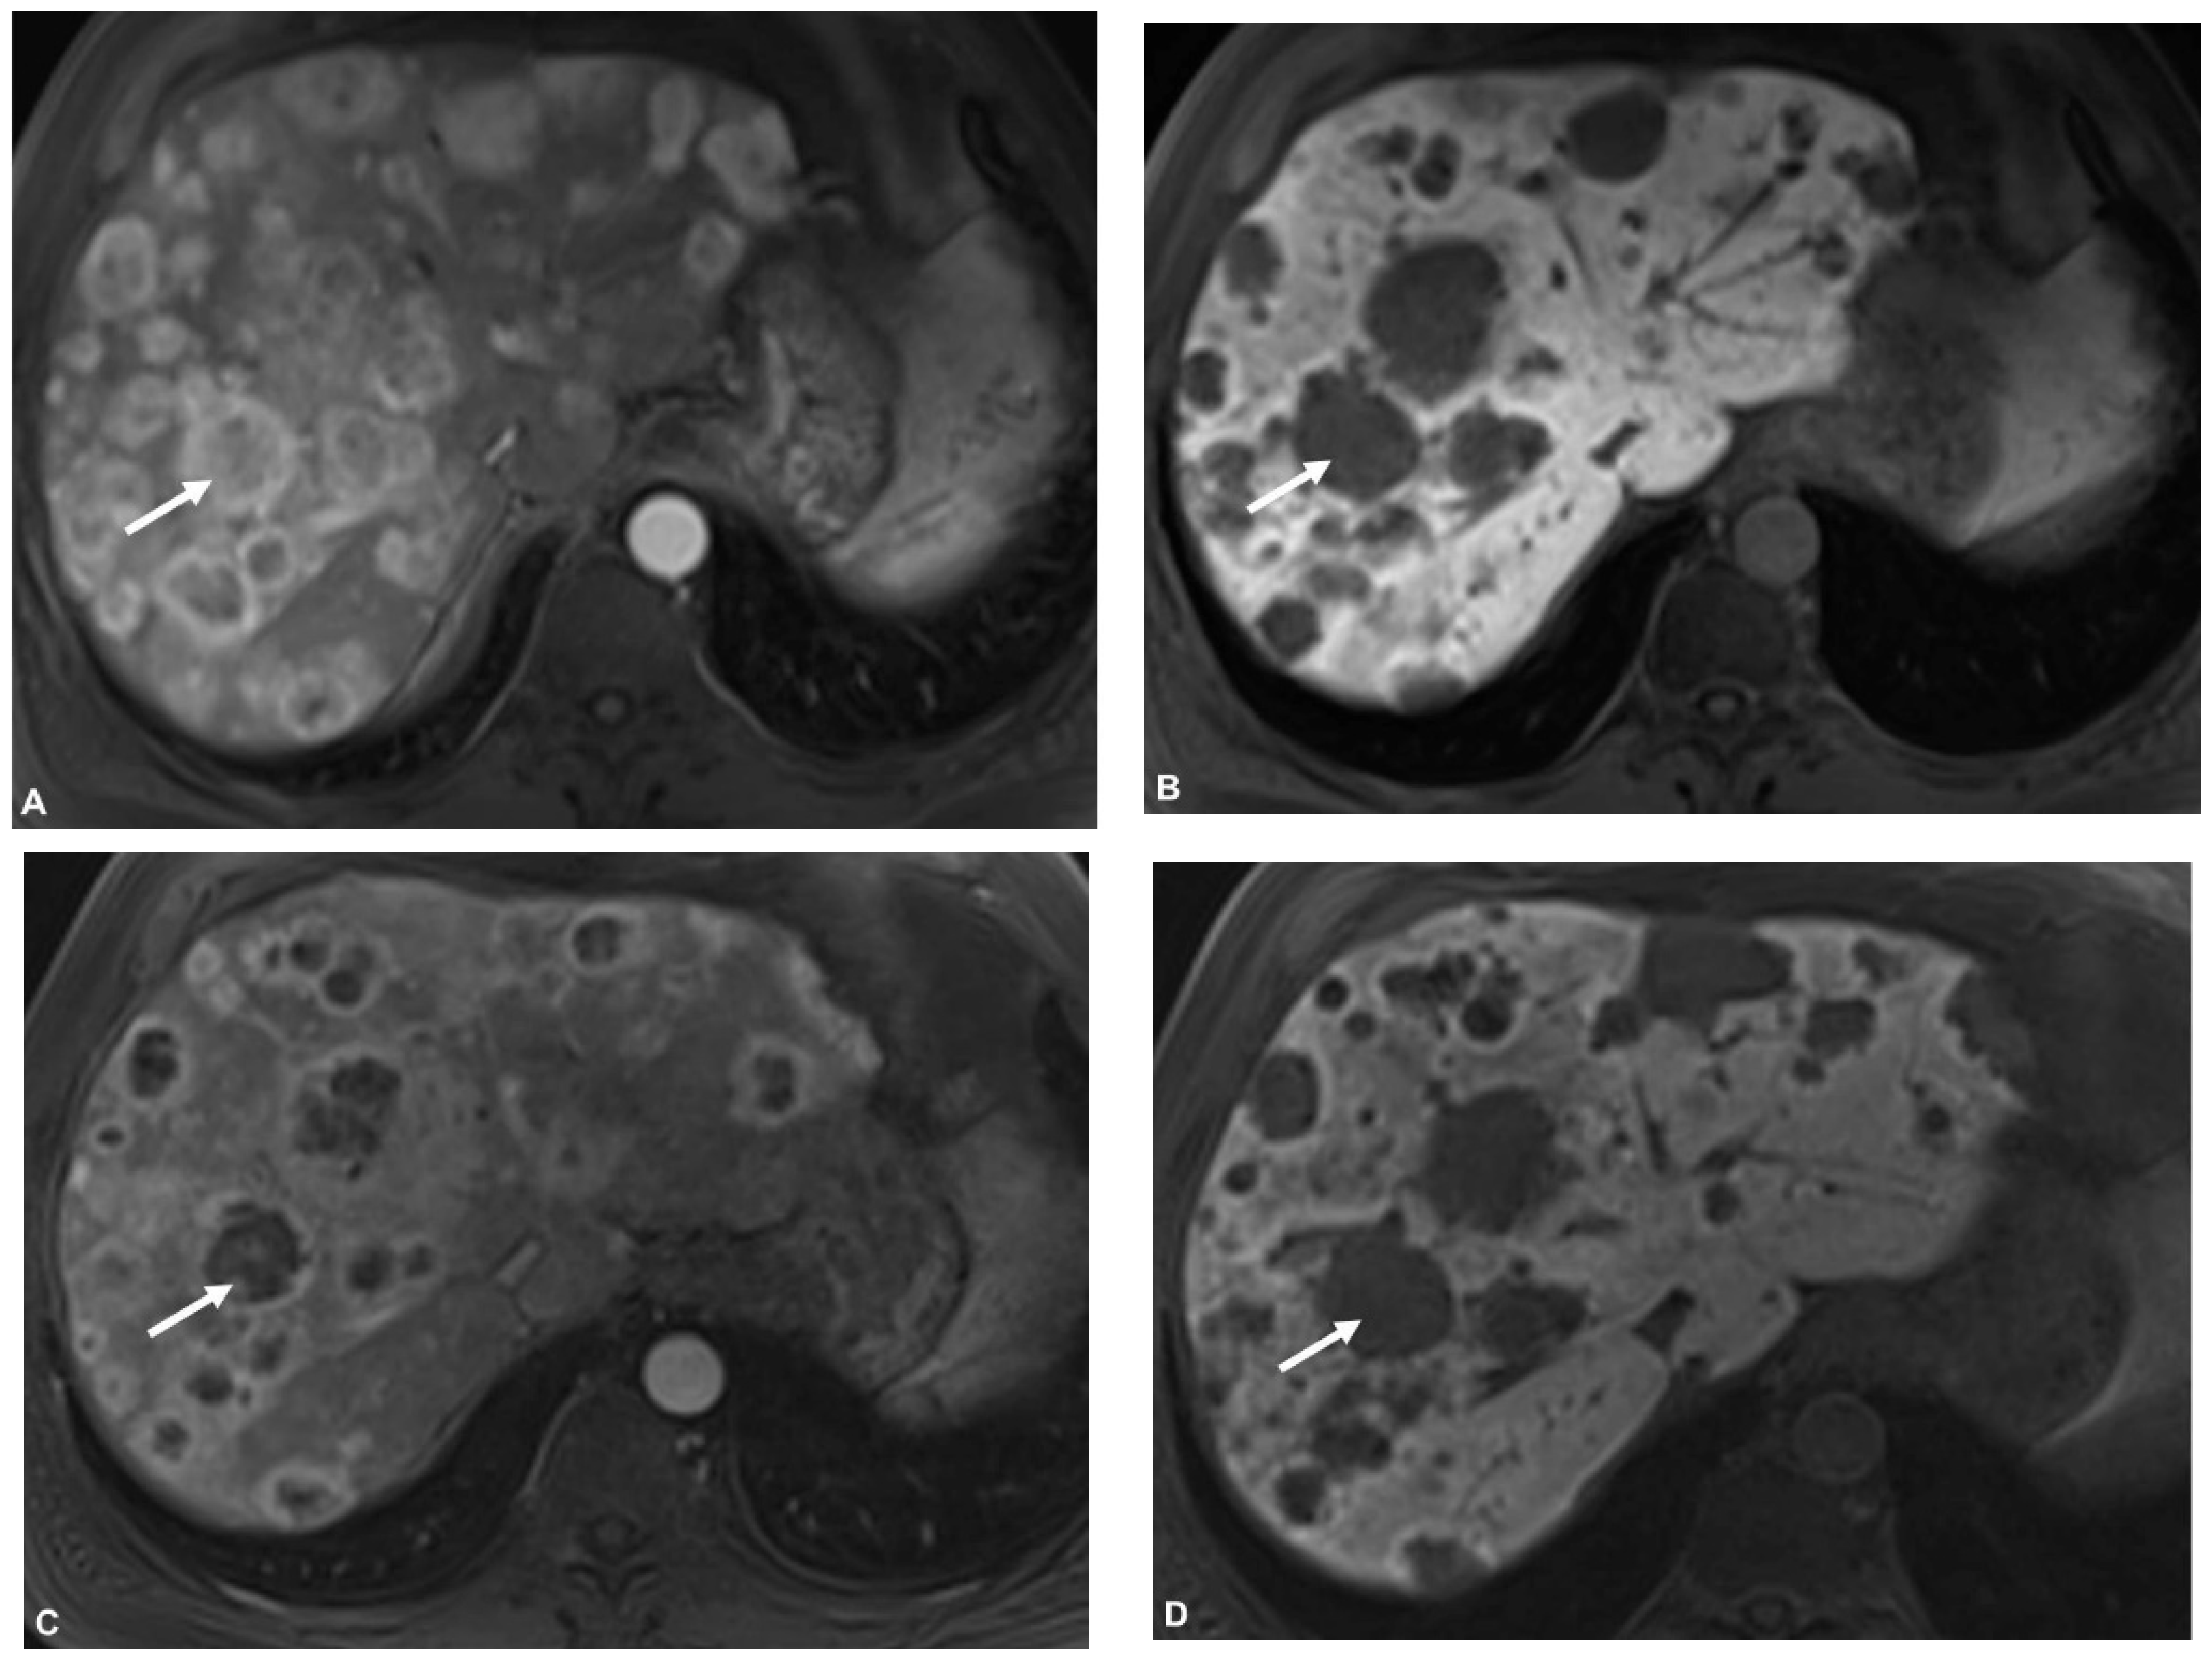

3.3. Response Assessment on First Follow-Up

3.4. Response According to HPFS > 6 Months

3.5. Response According to HPFS > 12 Months

3.6. Response According to HPFS > Median (720 d)